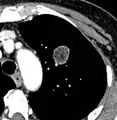

A "notch sign".[9]

A triangular perifissural node can be diagnosed as a benign lymph node.[9]